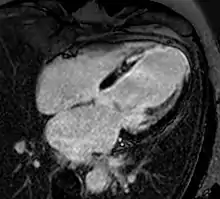

![]() نمونه ای از تصاویر CMRدر جهتهای مختلف تومور قلبی - در این مورد، میگزوم قلبی.[1] | |